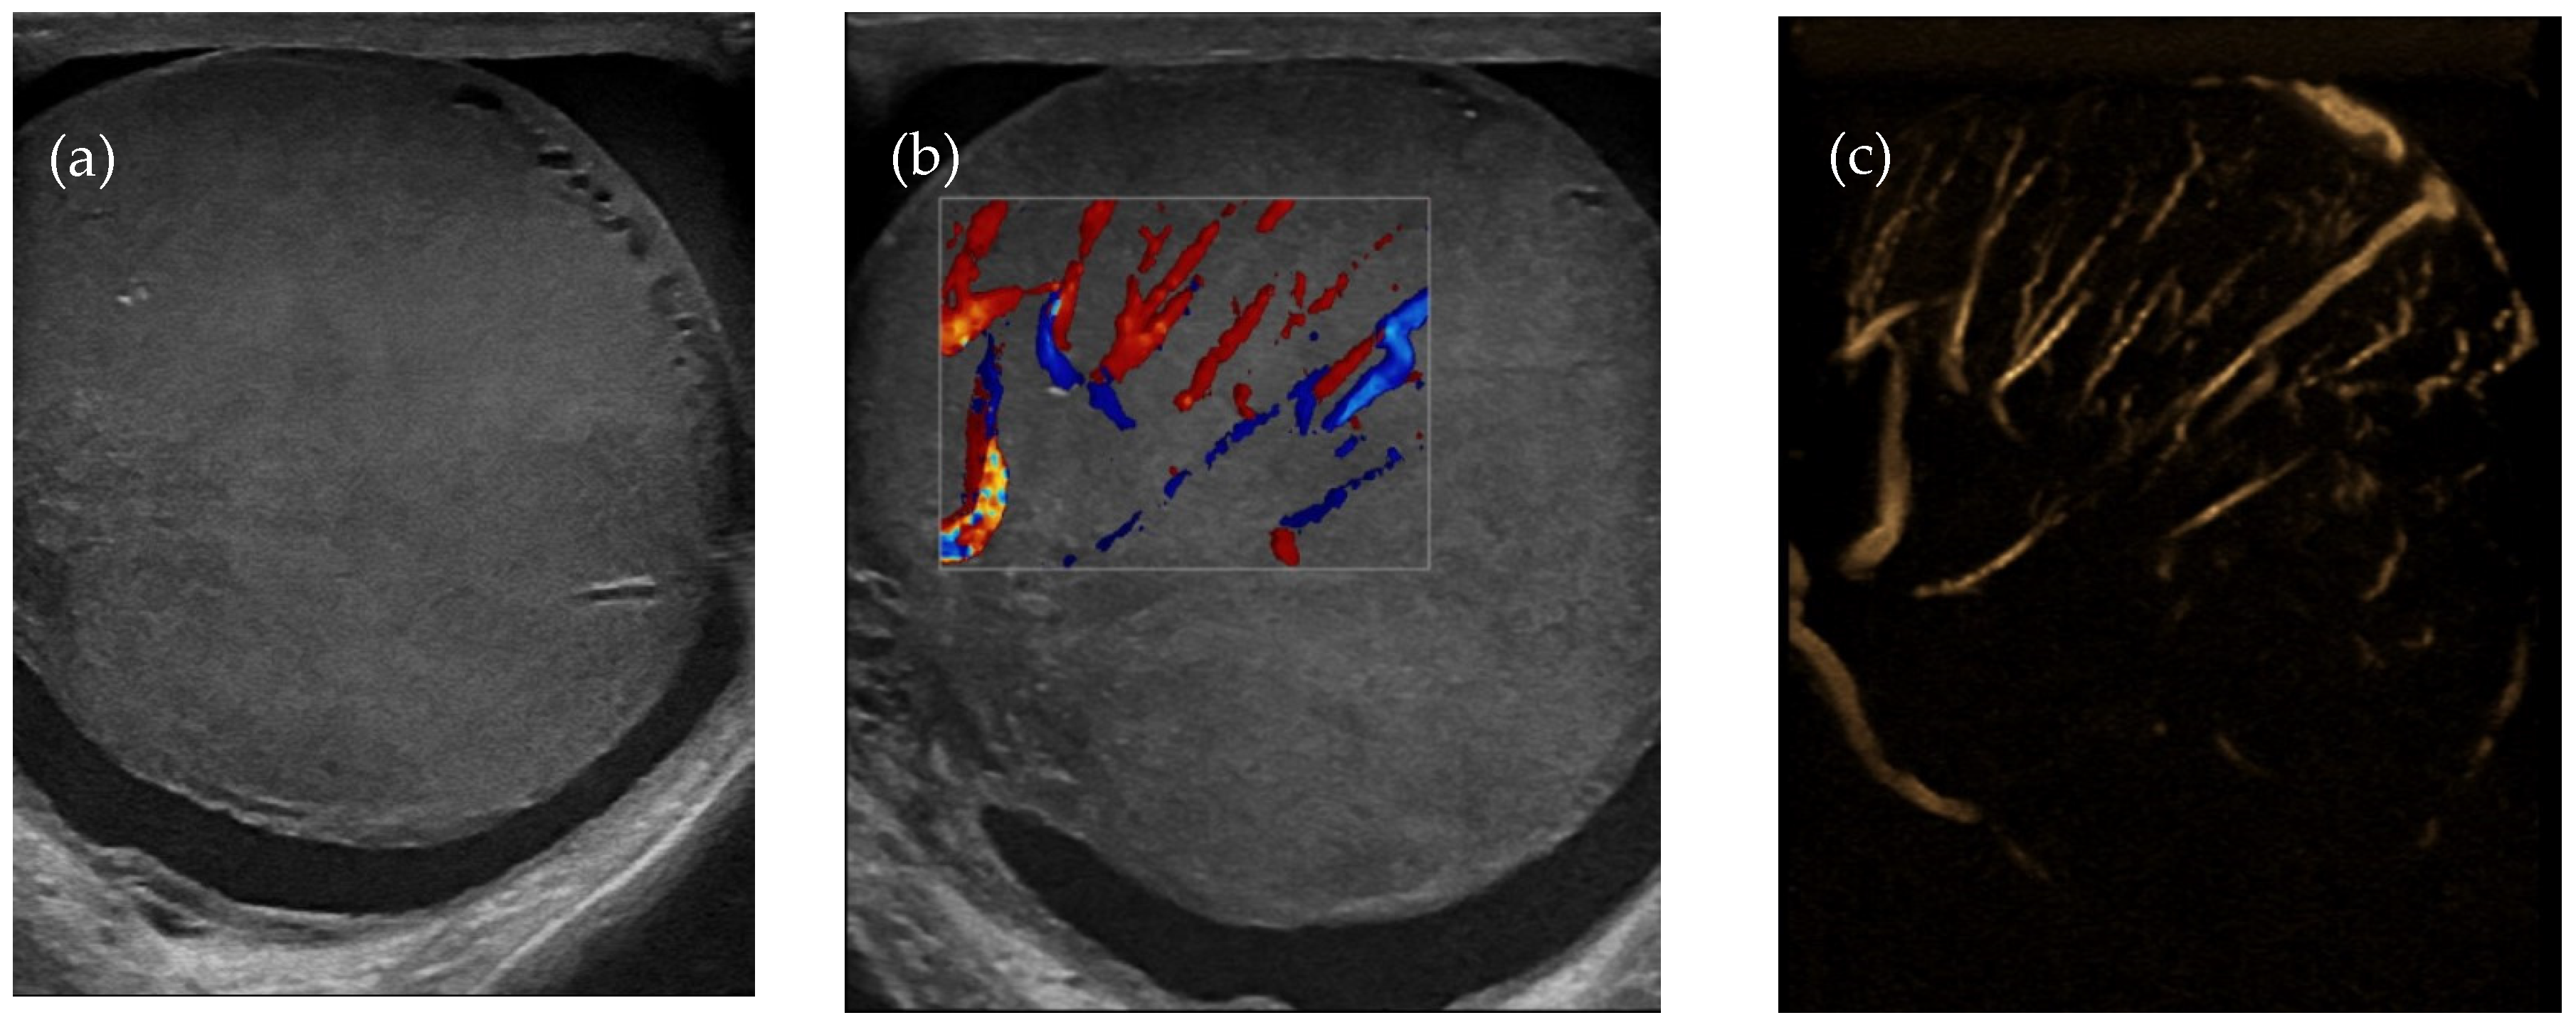

Given the history of ALL and the patient’s symptoms, a monitoring CT scan (Figure 1a,b) was performed to assess any eventual organ relapse.

A contrast-enhanced CT scan of the thorax, abdomen, and pelvis was performed, showing an enlarged left testicle (ca. 100/60/60 mm) with increased native densities (Figure 1a), rich peripheral vascularity, discreetly iodophilic in nature, with peri-testicular fluid accumulation and epididymal contrast uptake at the level of the spermatic cord and scrotum on the left, and tissular nodules with heterogeneous iodophilia along the course of the left testicular vein to the level of the left renal hilum, in keeping with adenopathy (42/26/36 mm underlying the left renal hilum, 31/27/54 mm and 13 mm, respectively Figure 1b).

Figure 1. This is a figure of abdominal–pelvic contrast-enhanced CT in the coronal plane with (a) an enlarged left testicle and (b) adenopathy on the left testicular vein pathway.